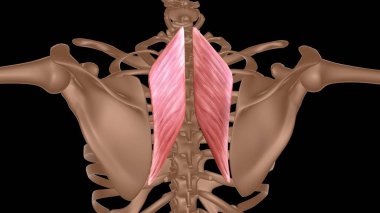

Tıbbi konsept 3 boyutlu illüstrasyon için insan kadın kas anatomisi

KasBileşenlerDorsalfleksörPalmarbrachiiBrevisLongusabdüktöradductorekstansiyonOrasına3d oluşturma3B illüstrasyonCarpiteresdeltoideusDigitorumbrachioradialiskomplikasyondigitiquintipollicisprofundusulnarispronatorPalmarisinterosseiopponenscoracobrachialisKas Anatomisilongus muscleinterossei musclebrevis musclelummbrical muscletricep mucslepollicis musclesuperficialis muscleBenzer İçerikler